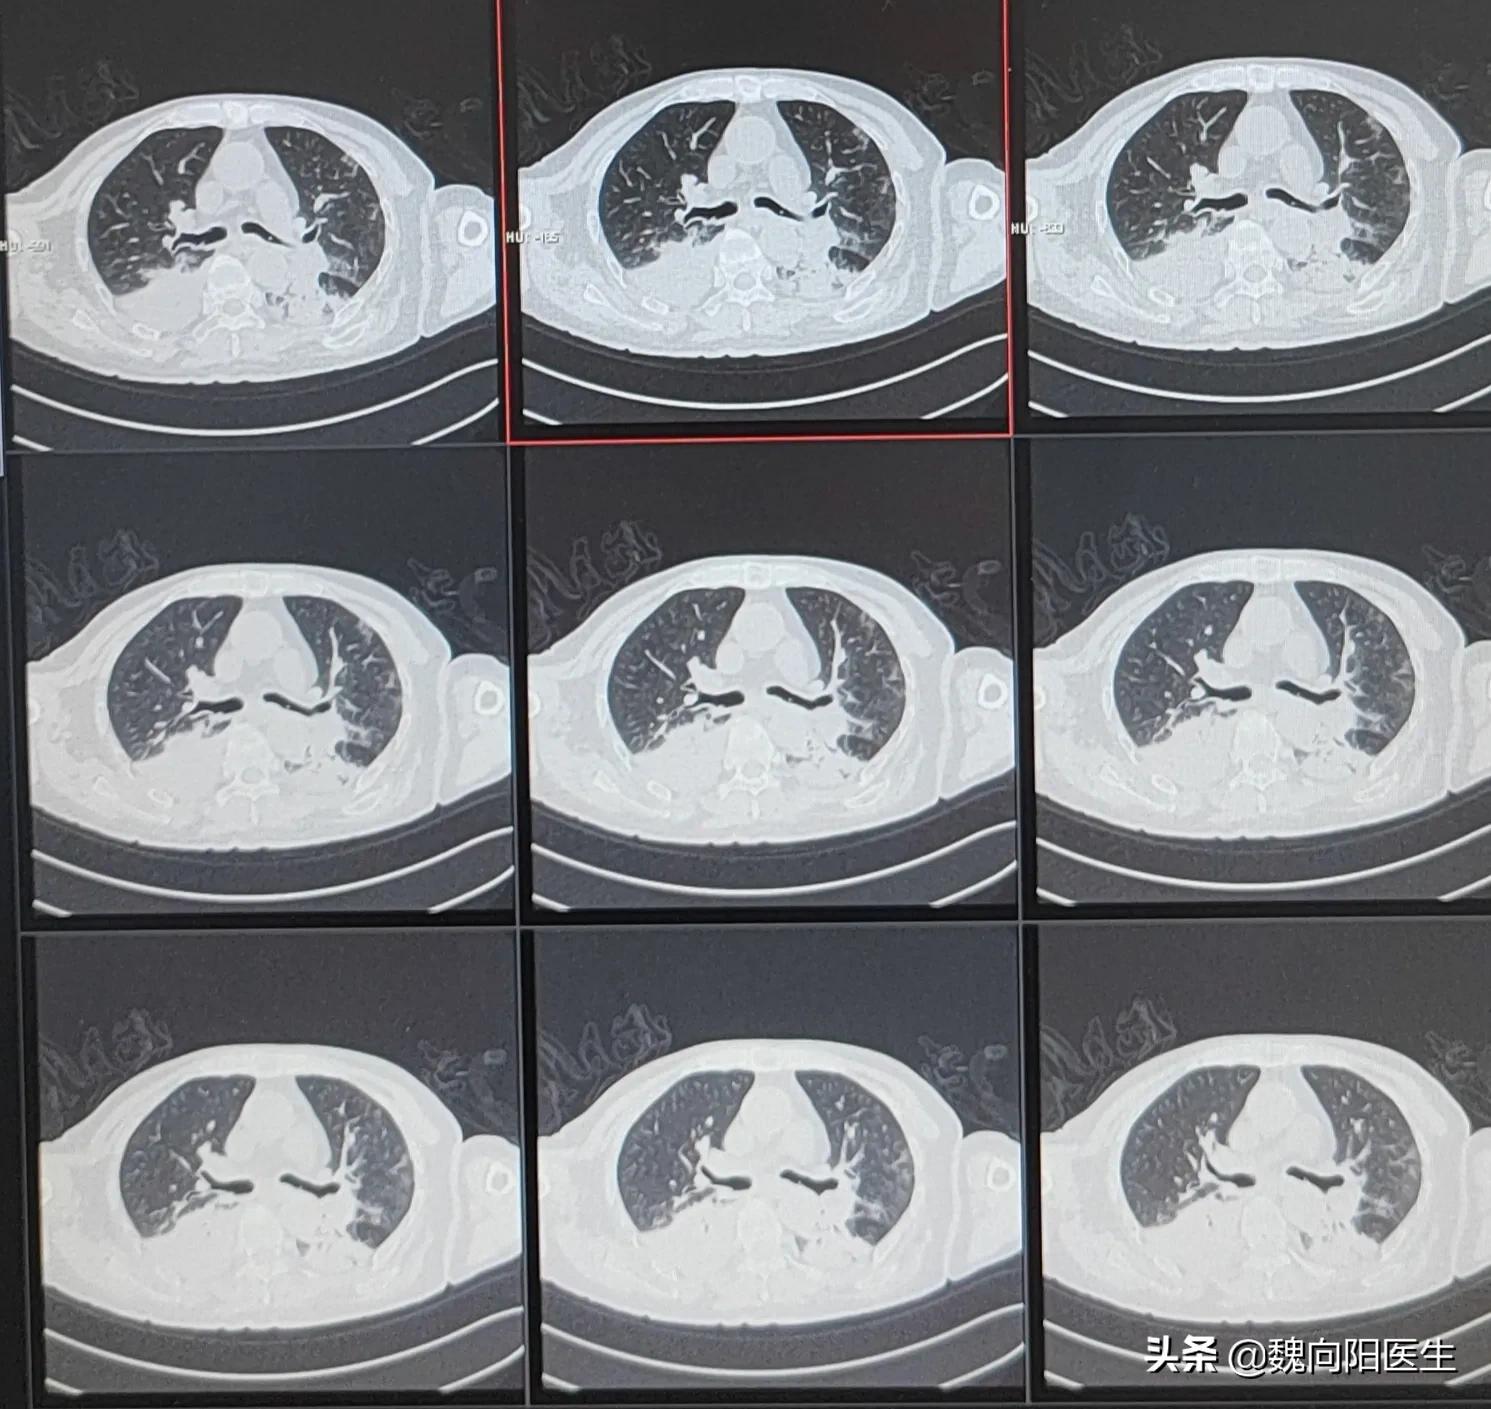

下胃管的目的是为了尽可能的引流出咖啡色胃液,以防胃液反流引起,引起吸入性肺炎。

肺部感染

对于没有咖啡色胃液的患者,可以及早进行胃管进食。尽可能维持肠道菌群的稳定,以防肠道菌群移位引起二次感染。